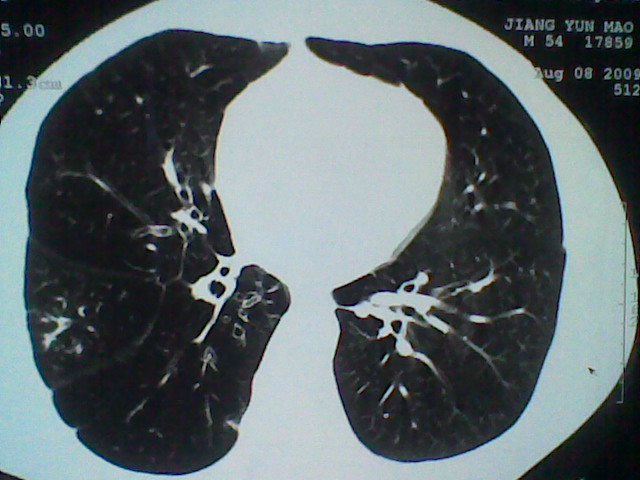

标题: CT21512:支扩伴感染?

患者女。咳嗽数天,咯血半天。

我们报的是支扩伴感染?

支持 支气管扩张并感染。

支持楼主意见,考虑支气管扩张并感染。

支气管扩张并感染。

支持楼主意见,还有肺气肿